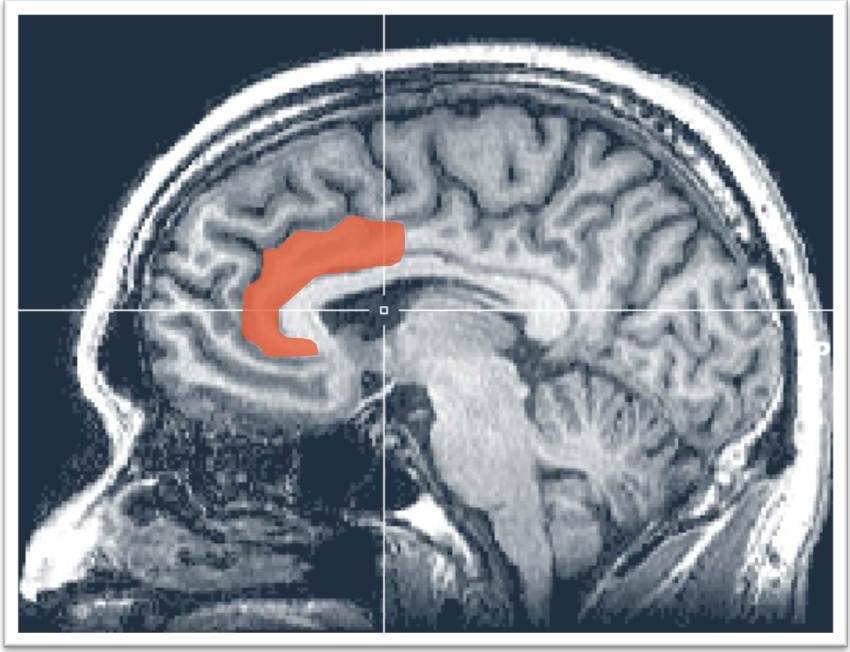

New research in primates has shown for the first time that counterfactual thinking is causally related to a frontal part of the brain, called the anterior cingulate cortex. And scientists have proven that the process can be changed by targeting neurons (nerve cells) in this region using low-intensity ultrasound.

If neurons in the anterior cingulate cortex are not working properly, then it would not be possible to switch to alternative options, even when these alternatives are the best available. Scientists believe that this is what happens in some psychiatric conditions where people are stuck in dysfunctional habits.

After showing that the cingulate cortex was linked with remembering which option was best, researchers used low intensity ultrasound to modulate the activity in this brain region and see its effect on behaviours. When the neurons were stimulated, their counterfactual thinking was impaired.

“This is a really exciting study for two main reasons – firstly because we discovered that the cingulate cortex is crucial to help switch to better alternatives, and secondly because low-intensity ultrasound can be used to reversibly change brain activity in very precise part of the brain,” she said.